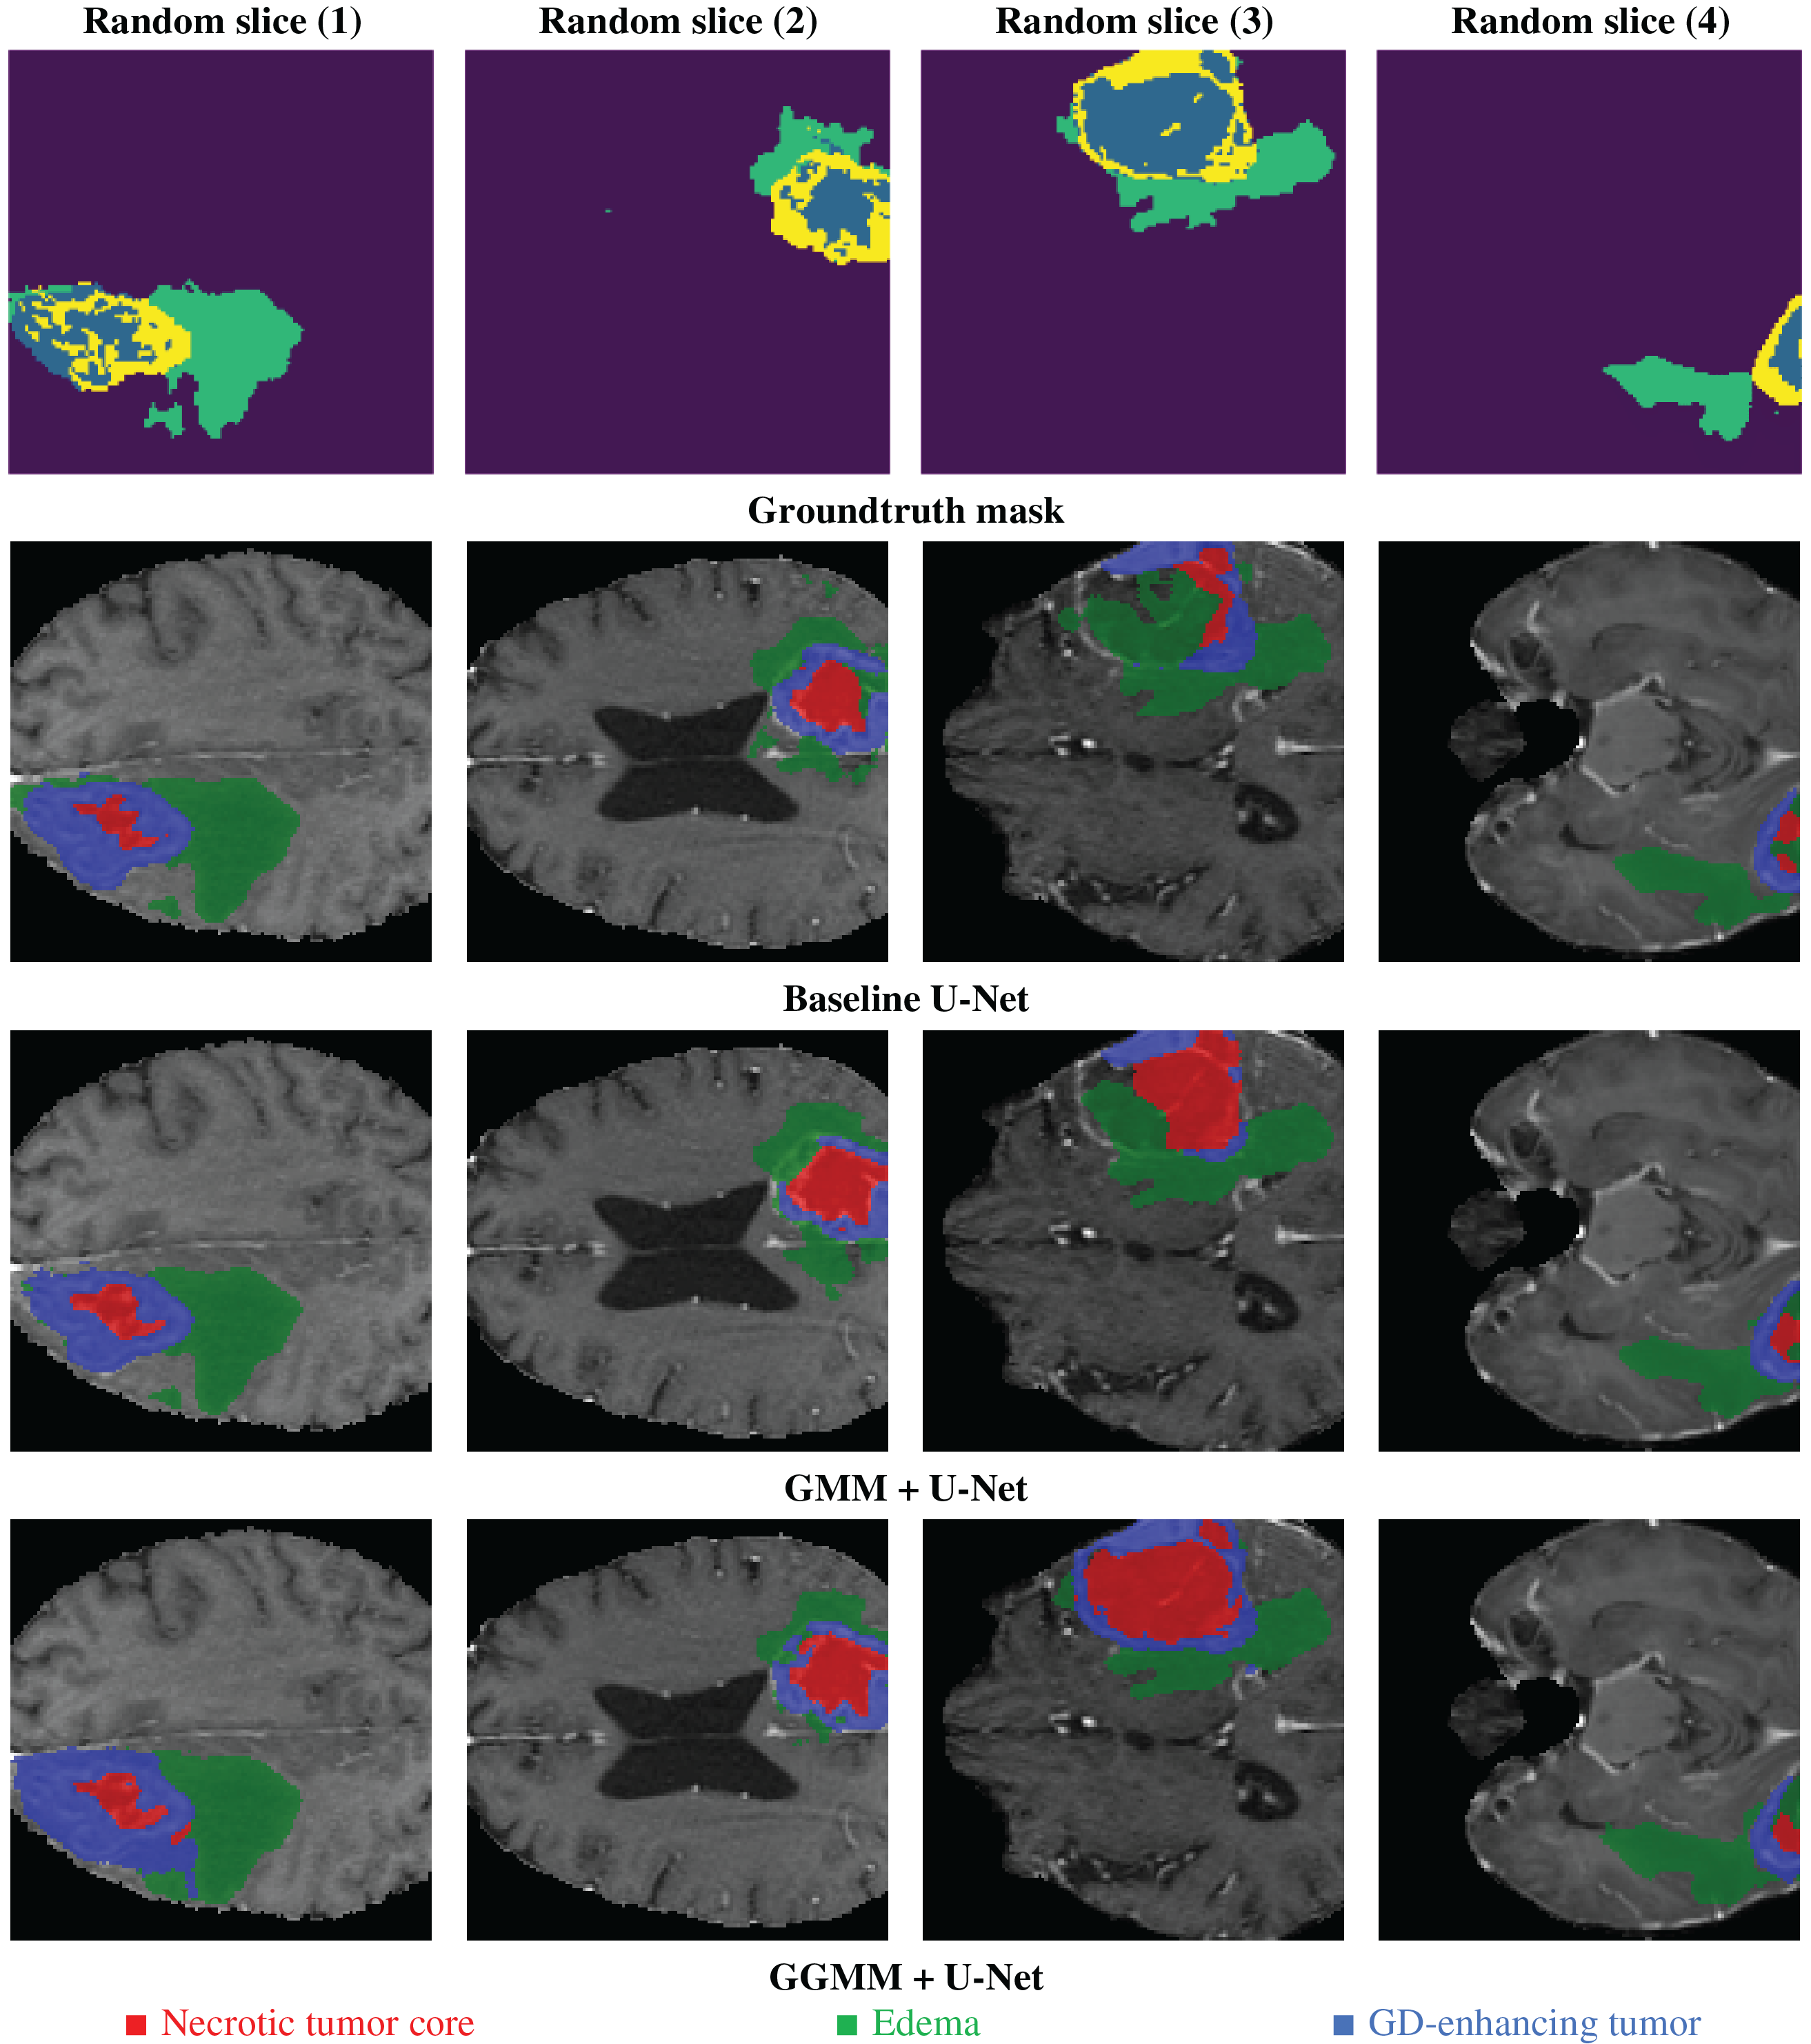

Fig. 13 shows the processing step results for the same 4 random slices shown in Fig. 1; the predicted results are presented for the 3 models trained by 50 epochs. The base U-Net configuration, as we can notice in the figure, detects the general tumor area. However, it fails to define at the edge, particularly within the necrotic core, resulting in a trespassing effect on nearby structures like edema or GD-enhancing region. This baseline U-Net model has a general shape for edema but no fine details at the boundaries, this can affect the accuracy of assessing peritumoral edema. Although the model is fairly good, its inability to recognize accurate boundaries compromises its potential in analyzing fine tumor structure. However, it is still very good at detecting the whole tumor. The GMM pre-segmented channel configuration enhances segmentation accuracy for the necrotic tumor core; it delivers more defined details than the baseline U-Net. However, we notice some overlaps and incomplete edges. For edema, the model setup shows modest improvements yet remains somewhat limited in contrast sensitivity in identifying the GD-enhancing tumor. This model addition may not help fully capture the variable MRI contrasts in certain areas, impacting the accuracy of GD-enhancing tumor segmentation.

Figure 13: Example of predicted segmentation for 04 random slices for the three 03 trained models

The GGMM pre-segmented channel configuration produces sharp and highly precise segmentations, particularly for the necrotic tumor core, which is distinctly delineated with high boundary accuracy. This improvement is attributed to GGMM’s flexibility in modeling diverse MRI contrast levels. In the case of edema, the model demonstrates enhanced detection capabilities, enabling precise separation from adjacent tissues and facilitating clearer identification of peritumoral edema. Additionally, the GD-enhancing tumor region is accurately isolated with minimal overlap, making the model highly effective for reliable and accurate tumor segmentation.

The results clearly indicate that the GGMM + U-Net configuration outperforms both the standard U-Net and the GMM + U-Net in terms of segmentation accuracy. This is evident in its ability to produce more sharply defined edges for both the necrotic tumor core and edema, enabling better differentiation between tumor subregions. Moreover, the model exhibits enhanced sensitivity to contrast variations, an essential factor in the accurate detection of tumor structures, thereby improving the overall reliability of the segmentation. Furthermore, the GGMM + U-Net precisely delineates GD-enhancing regions, which are critical indicators of active tumor growth. These capabilities make the GGMM + U-Net architecture highly suitable for applications that demand high segmentation accuracy, such as treatment planning and disease monitoring in clinical settings. Its improved performance has the potential to enhance diagnostic accuracy and enable more personalized therapy, ultimately contributing to better patient outcomes.